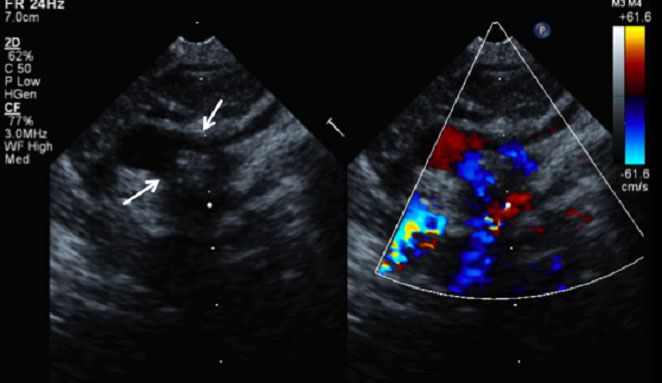

Figure 2.

A double aortic arch vascular ring is composed of a dominant right aortic arch (lower arrow) and a smaller left aortic arch (upper arrow).

Echocardiography is used liberally in evaluating patients for vascular ring anomalies because it may be adequate for diagnosis4 and is less invasive than other modalities (Figure 2).7 Although the double aortic arch vascular ring anomaly usually occurs without associated cardiovascular anomalies,4,11 echocardiography provides the added ability to rule out intracardiac anomalies.4